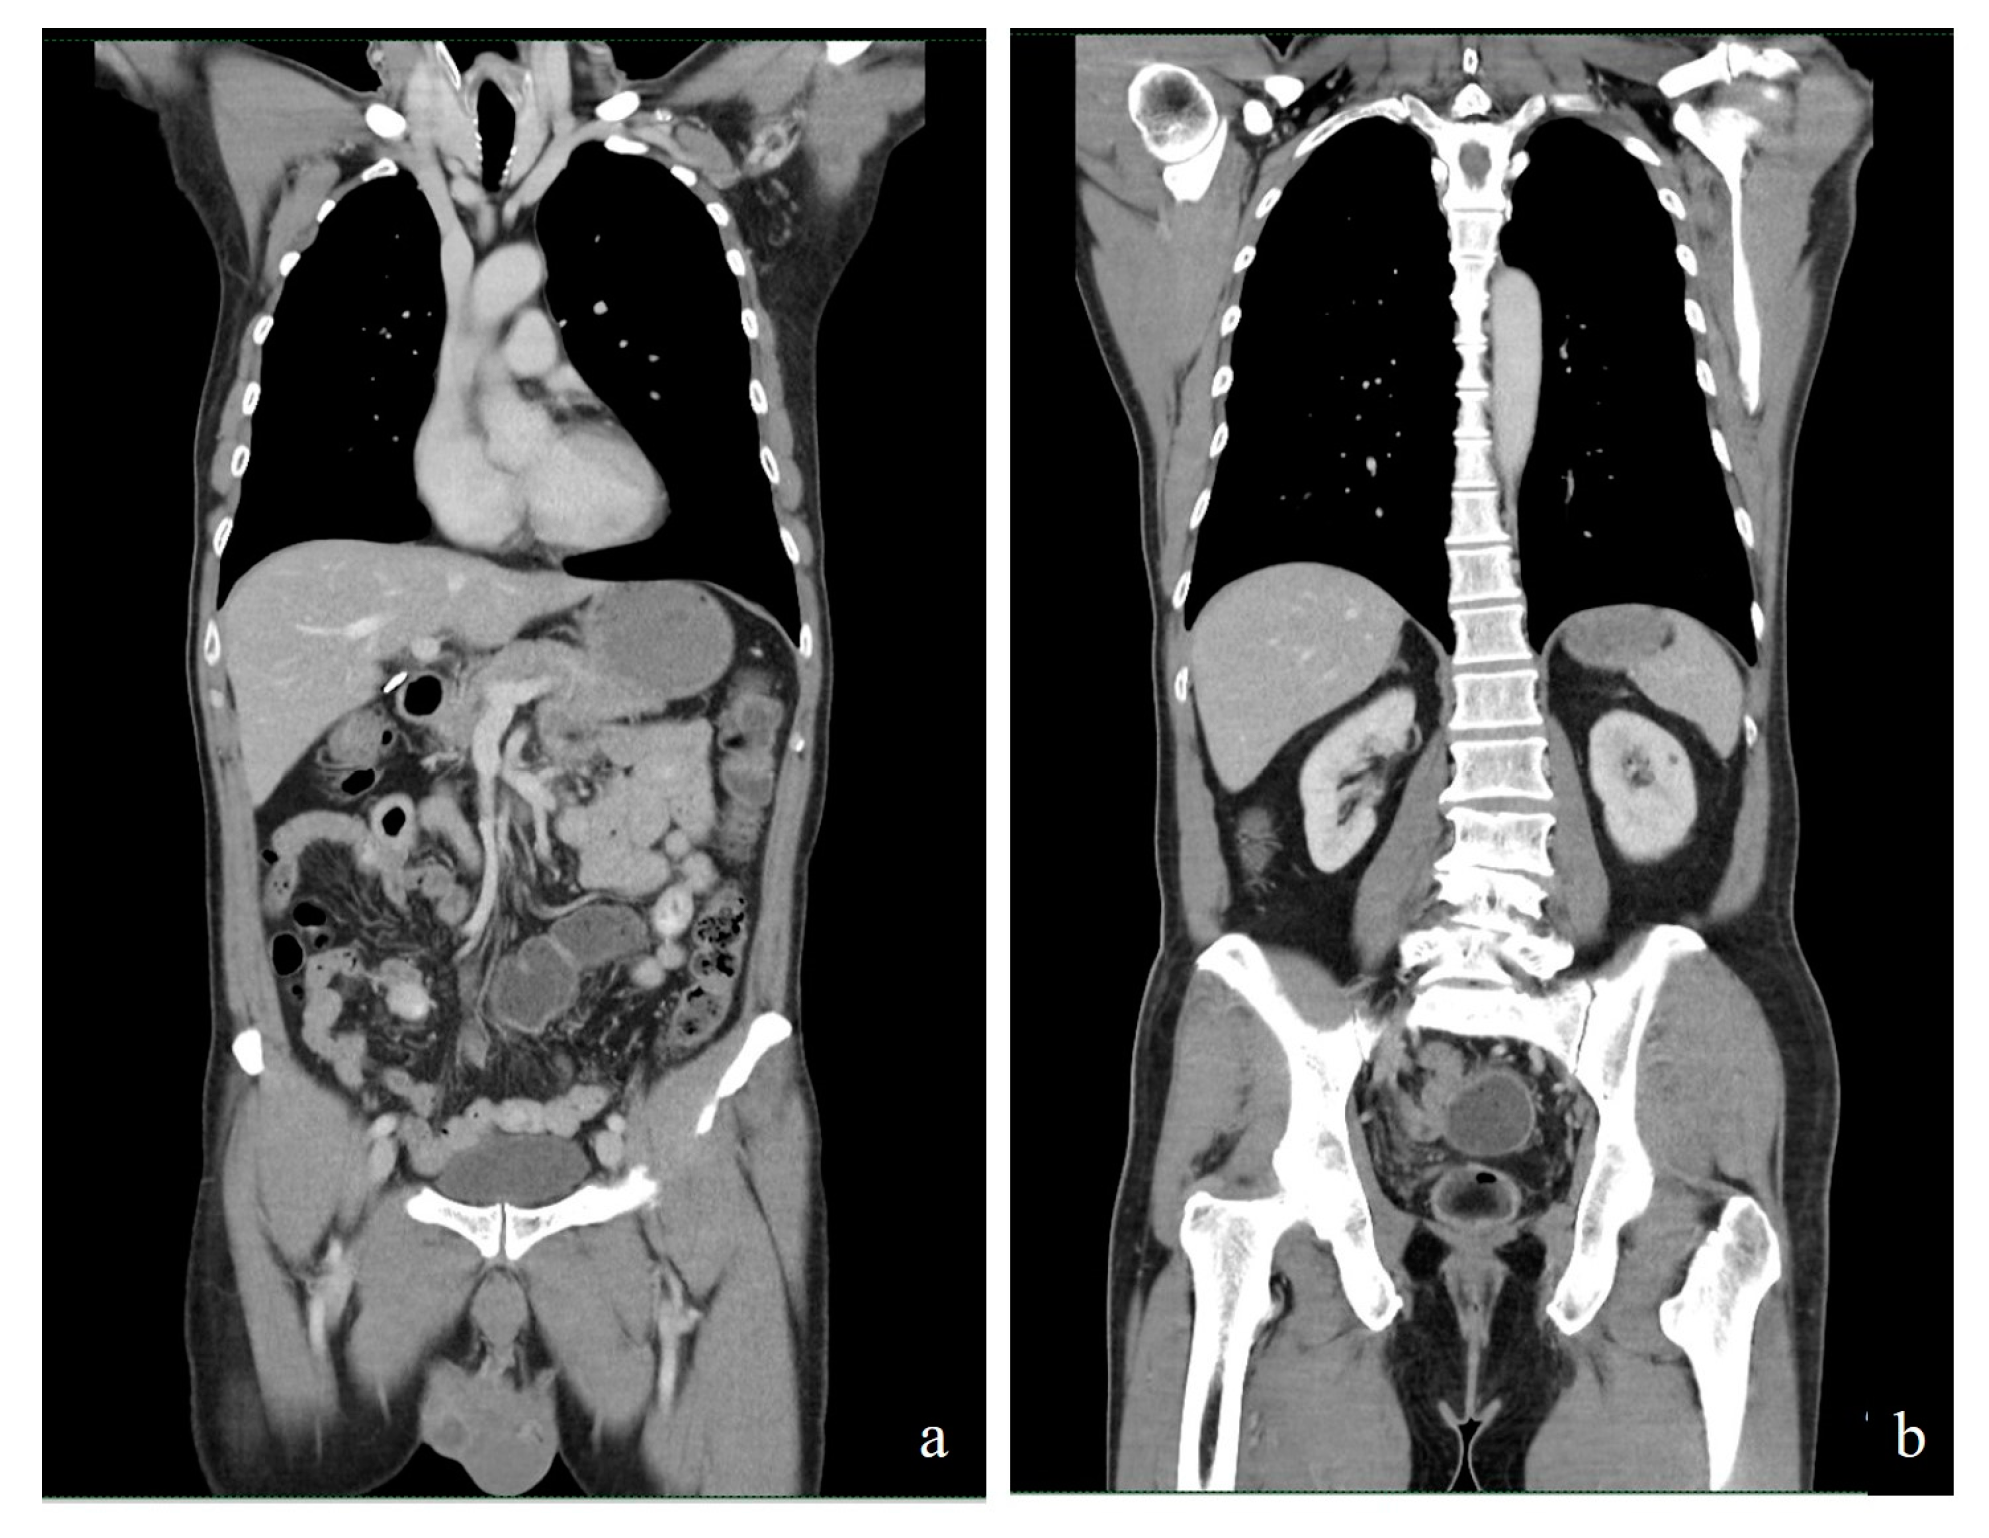

2. Case Report